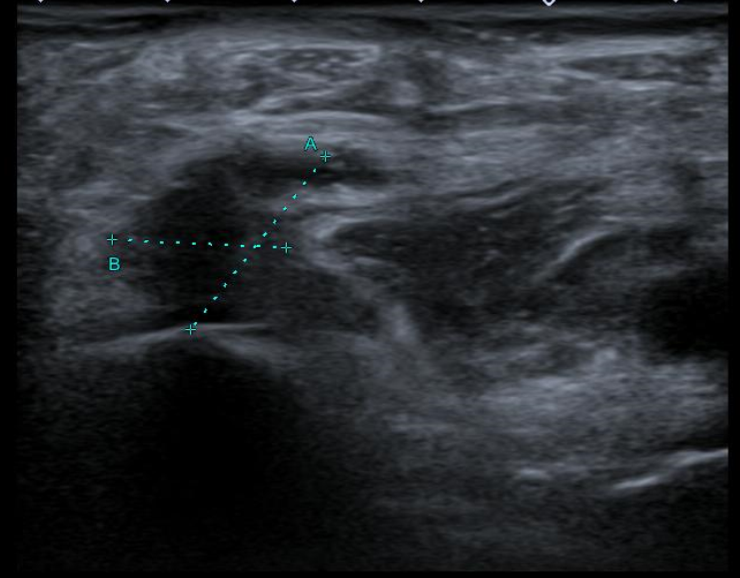

Ecografía Doppler miembros inferiores: venas permeable sin signos de TVP. En el hueco poplíteo de MID se observa una estructura anecoica de aproximadamente 17 x 14 mm (AP x T), con restos hiperecogénicos en su interior y cuyo polo inferior muestra una morfología irregular afilada, observándose láminas de líquido adyacentes. Hallazgos compatibles con rotura de quiste popliteo (de Baker).